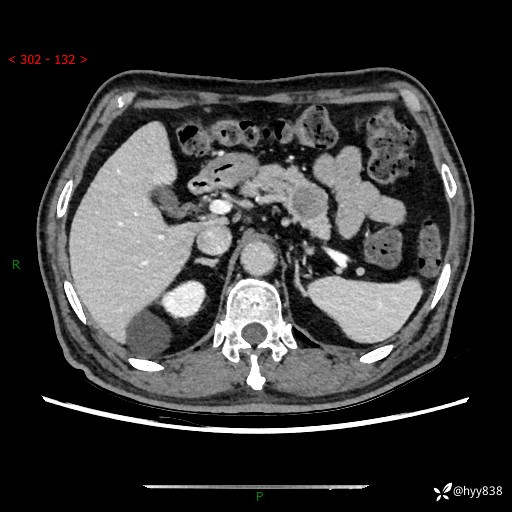

69岁/男,四肢无力3月余。胰腺囊实性占位,渐进性强化---结果公布~

【患者信息】:69岁/男

【主诉】:四肢无力3月余。

【现病史及既往史】:患者3月前无明显诱因出现四肢乏力,伴有口干、多饮、多尿等症状,无畏寒、发热、恶心、腹痛、腹泻等其他症状,于2024-06-13来我院住院治疗,完善相关辅助检查后,考虑“2型糖尿病”,予以降糖(阿卡波糖片 50mg po tid、德谷门冬双胰岛素注射液 8iu 早餐前 皮下注射)等治疗,口干、多饮、多尿较前缓解,血糖控制可;现仍存在四肢乏力,于2024-08-28来我院门诊就诊,查血钾2.88 mmol/L ,现以“低钾血症”收入我科。 本次起病以来,患者精神、饮食、睡眠良好,二便正常,近3月余体重下降约5kg。

【检查】:胰腺CT平扫+增强